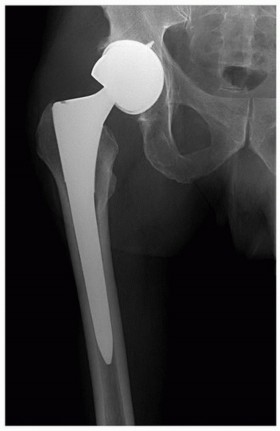

INDICATIONS Total hip replacement (THR) in the setting of developmental dysplasia of the hip (DDH) is indicat…

Total Hip Arthroplasty in Patients with Proximal Femoral Deformity INTRODUCTION Proximal femoral deformity in…